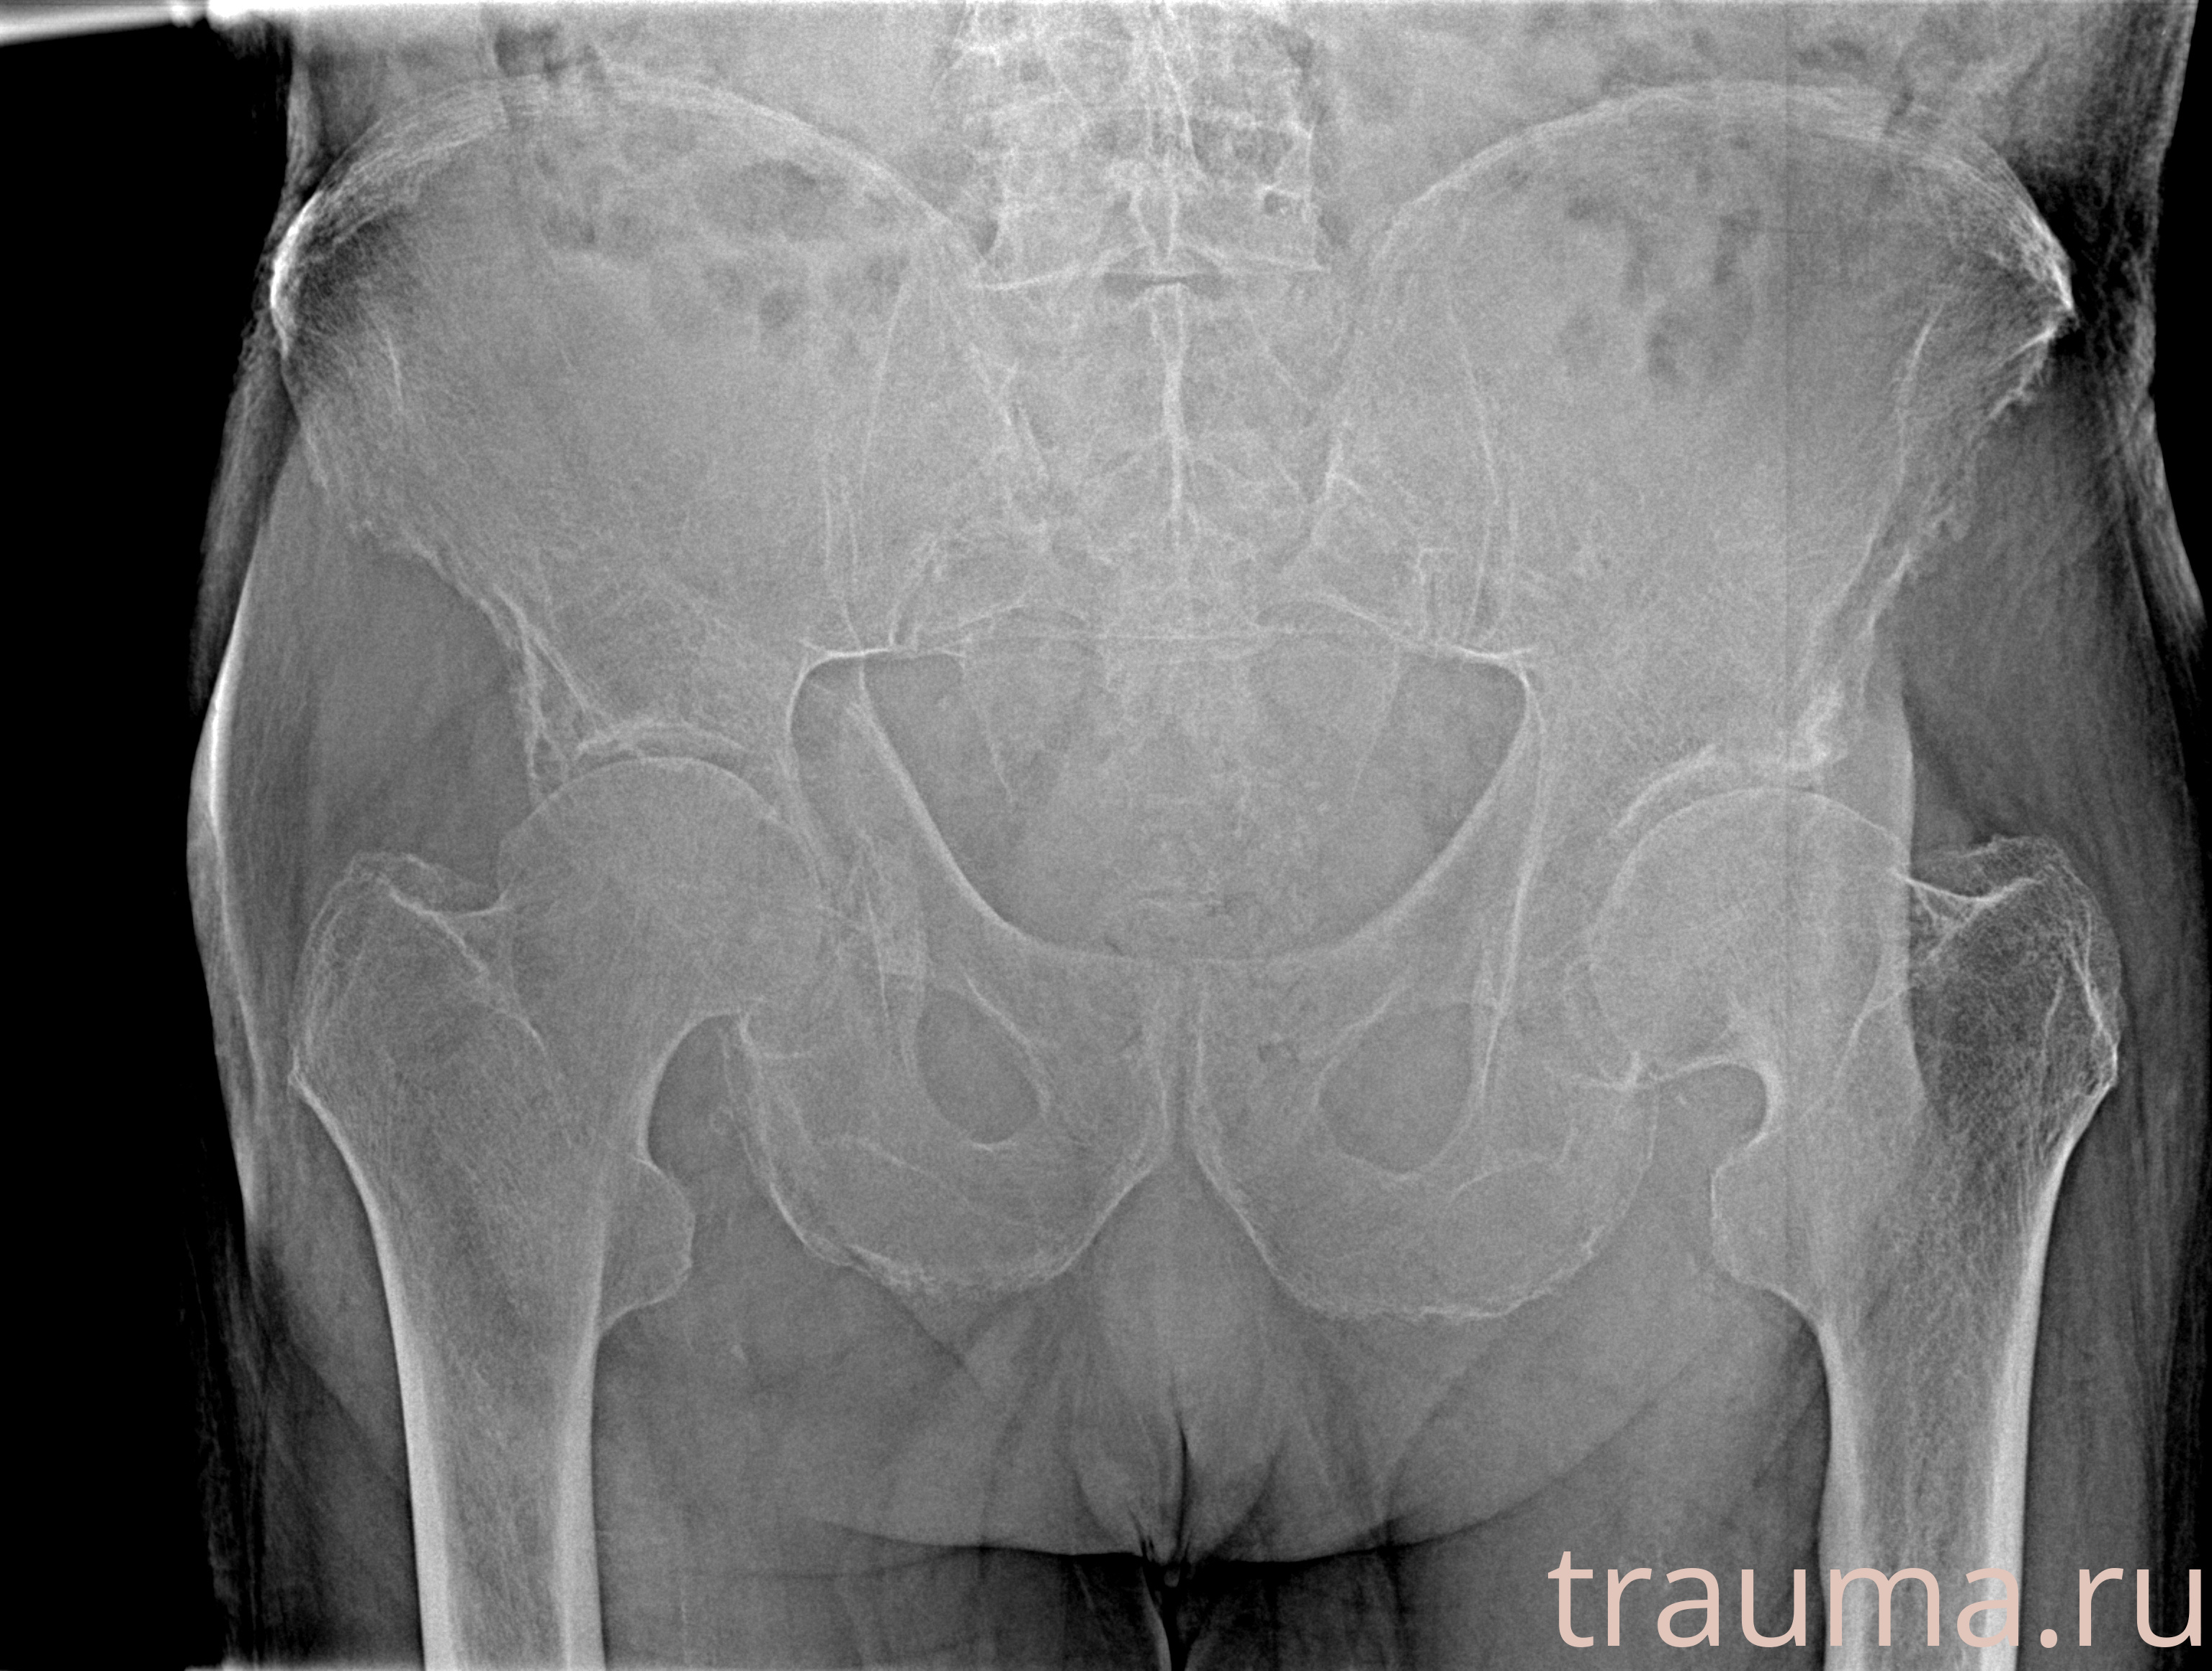

Рентгенограммы

Рентген на дому: по вашему адресу приезжает врач-рентгенолог, травматолог-ортопед с мобильным рентгеновским аппаратом, проводит диагностику травмы или заболевания, делает необходимые рентгенограммы, дает рекомендации по дальнейшему лечению. Получить качественные снимки в домашних условиях возможно благодаря уникальной методике, разработанной МосРентген Центром для института  Склифосовского